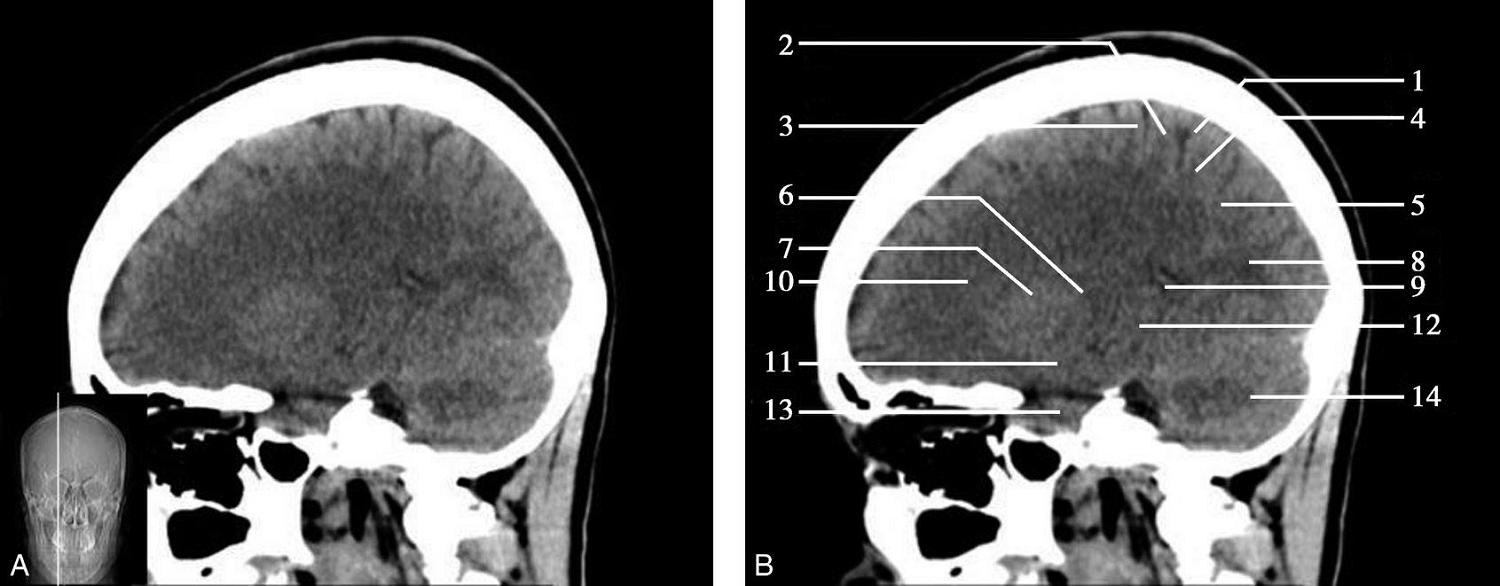

重要结构:卵圆孔、棘孔、破裂孔、斜坡、颞骨岩部、颈静脉孔(图1-2-1、图1-2-2)。

图1-2-1 颅底层面

A.横断面;B.横断面标注

1.晶状体;2.筛窦;3.颞肌;4.中颅窝底;5.外耳道;6.延髓;7.乙状窦;8.小脑半球;9.眼球;10.眼眶;11.上颌窦;12.蝶窦;13.乳突;14.耳郭;15.小脑蚓部;16.枕内隆凸

图1-2-2 颅底层面(骨窗)

1.鼻骨;2.筛窦纸板;3.颧骨眶突;4.翼腭窝;5.蝶骨大翼;6.卵圆孔;7.破裂孔;8.颞骨颧突;9.棘孔;10.斜坡;11.颞骨岩部;12.乳突;13.颈静脉孔;14.枕乳突缝;15.枕骨;16.枕内隆凸

层面前部呈开口向前的“V”字形,正中为鼻中隔,向两侧依次为筛窦和眼眶,眼眶内前部为眼球,后部为眶脂体。翼腭窝位于眼眶后部,窝内含有脂肪并有上颌神经通过。层面中部为蝶骨体,蝶骨体中部可见含气蝶窦,蝶窦后方为枕骨基底部,两者呈前后关系,其上面构成斜坡。蝶窦两侧为蝶骨大翼,其后外侧缘处由前向后可见卵圆孔和棘孔,分别有下颌神经和脑膜中动脉通过。斜坡外侧、岩骨尖前方为破裂孔。蝶骨大翼与眶外侧壁的颧骨借颧弓相连,颧弓和蝶骨大翼之间有咬肌及颞肌。层面中部外侧为外耳道。颞骨岩部呈“八”字形,相互之间借破裂孔软骨、蝶岩软骨结合和岩枕软骨结合连接。岩部后外侧的乳突部内可见乳突小房,乳突部与枕骨相接。岩骨后部可见颈静脉孔,内有颈内静脉、舌咽神经、迷走神经和副神经通过。层面后部为颅后窝,其内可见延髓,延髓前方为延髓前池,内有椎动脉,后外侧为小脑半球下部,后方为第四脑室、小脑扁桃体及小脑蚓部。

破裂孔、卵圆孔、棘孔及斜坡等均为重要的解剖结构,临床常见疾病如鼻咽癌常侵犯上述结构(图1-2-3)。颈静脉孔区较常见的肿瘤为颈静脉球瘤,常伴有颈静脉孔及其邻近骨质的破坏(图1-2-4)。